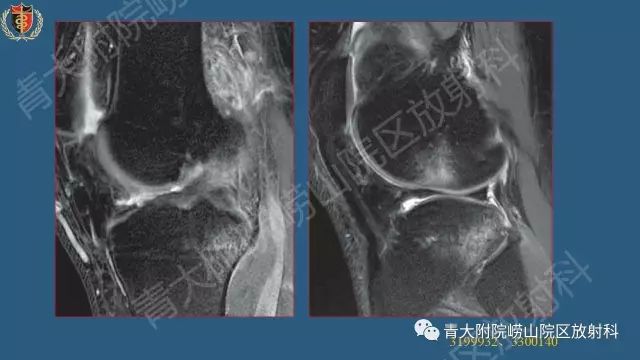

半月板损伤术前及修补术后MR影像学评价